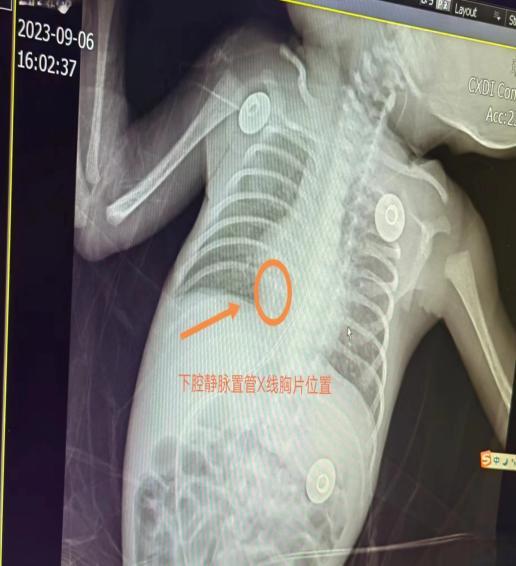

目前,新生儿PICC置管过程通常采用“盲穿”方式居多,穿刺前体表测量导管置入长度,穿刺后行胸部X片判断导管尖端位置,其等待和检查本身就存在一定的滞后性。因新生儿解剖上存在较大的个体差异,单单通过体表测量很难准确预测导管置入长度,且体表投影会受到诸多因素干扰,影响尖端位置的判断,如果导管位置需进一步调整,势必要重复拍摄X光片,加上重新调整导管位置延长了置管时间,增加了污染机会,导管相关性感染的风险也随之增高,特别是对于胎龄小、体重低的早产儿,过多的操作检查是一种不良刺激,容易引起生命体征的改变,甚至引发其他并发症。

腔内心电图定位技术(IE-ECG)是通过心电转换器将心房内心电图引导显示在显示器上,通过判断心电图P波的变化来确定导管尖端位置的一种技术。应用IE-ECG,可将PICC置管操作和定位于病床边一次完成,并能始终保持在无菌状态下,及时纠正导管异位,极大提高导管尖端定位的准确性,避免在X线照射下调整异位导管带来的损害,同时缩短了置管时间、提高护士工作效率,这对超低出生体重儿的治疗与抢救有着重大意义。